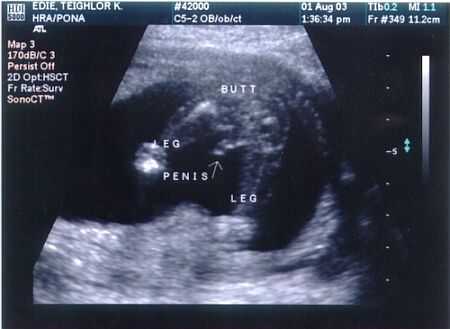

16 1/2 week ultrasound - Profile of babys spine, body and head. Heartbeat was 150 bpm and we found out its a ....

BOY!!